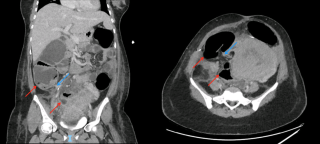

Case presentation

A 45-year-old man with no relevant past medical history presented with acute diffuse abdominal pain following a forceful sneezing episode. Physical examination revealed localized right-sided abdominal tenderness without peritoneal signs. Laboratory tests showed mild leukocytosis with normal inflammatory markers and hemoglobin. Contrast-enhanced computed tomography demonstrated a mesenteric hematoma associated with moderate hemoperitoneum and focal mural hypoenhancement of an ileal loop, without active arterial extravasation (Figure 1). Urgent surgical exploration revealed approximately 500 mL of hemoperitoneum, a large mesenteric hematoma, and an adjacent intestinal pseudodiverticulum (Figures 2-3). Segmental small bowel resection including the diverticulum was performed. Histopathological analysis confirmed fresh mesenteric hemorrhage and pseudodiverticular changes without evidence of malignancy, vasculitis, or vascular malformation. The postoperative course was uneventful, and the patient remained asymptomatic at six-week follow-up.